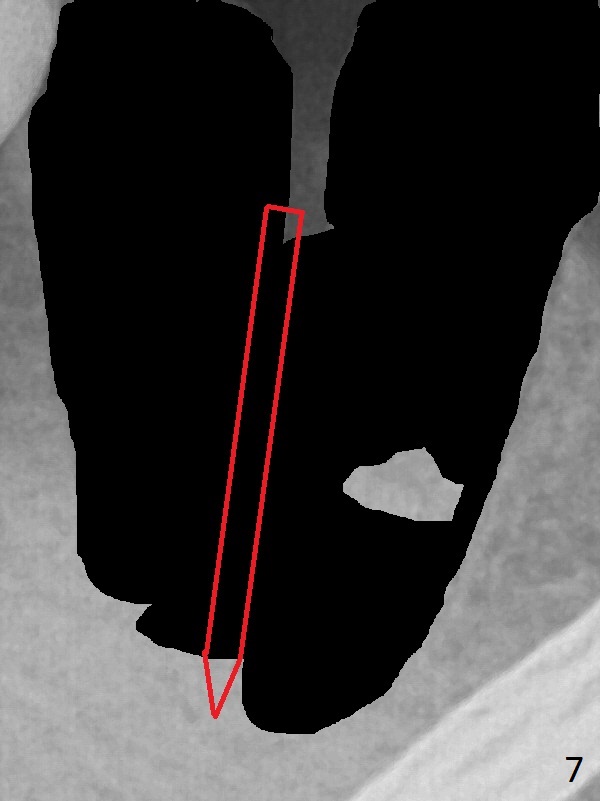

A 43-year-old man has residual roots at #30 (Fig.1). The mesial (M) and distal (D) roots approximates each other so close that the septum is thin (Fig.1,3-5). The latter is unfavorable for osteotomy. After extraction (Fig.5), the middle of the septum (Fig.8a (axial section of the sockets)) will be sectioned (Fig.6, 8b,c) prior to initial osteotomy (Fig.7,8d). The depth of the latter will be ~ 5 mm (Fig.2 red line) for a 13 mm (pink line) IBS implant.